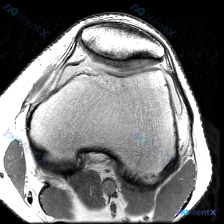

这是一张膝关节MRI的T1加权轴位图像,聚焦显示髌股关节及周围软组织结构,患者主诉提示存在软骨异常相关问题。

- 骨骼结构:股骨远端滑车、髁部皮质连续光滑,髓腔脂肪信号正常,无异常骨髓信号;髌骨形态完整,轮廓清晰,髓腔信号均匀,没有异常信号改变。

- 关节软骨:髌骨关节面软骨厚度尚可,轮廓光滑,信号符合T1序列正常表现;股骨滑车软骨显示清晰,没有明确局灶性变薄或缺失。

- 关节腔与周围软组织:关节腔内无明显异常积液;内外侧髌旁支持带走行正常,无增厚或连续性中断;腘窝前方软组织无肿胀、无异常信号。

基于当前这张切面的影像,没有观察到明确的异常病灶,所有结构的信号都符合正常解剖表现,也没有看到急性损伤(骨挫伤、韧带撕裂、关节积血)或者慢性退行性改变(骨赘、软骨下囊肿)的典型表现。